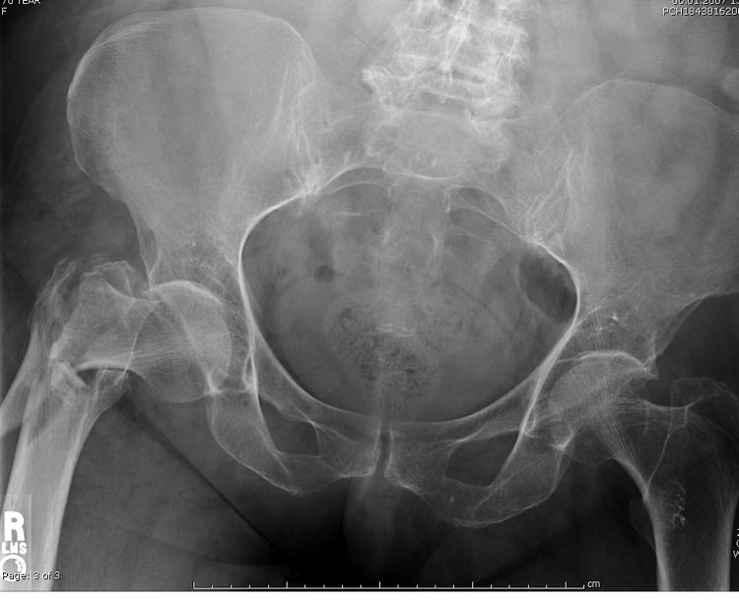

[Ortho] Чрезвертельный перелом бедра

Здесь 83 года, травма в результате падения

Имя     : #3 IT fx  injury.jpg